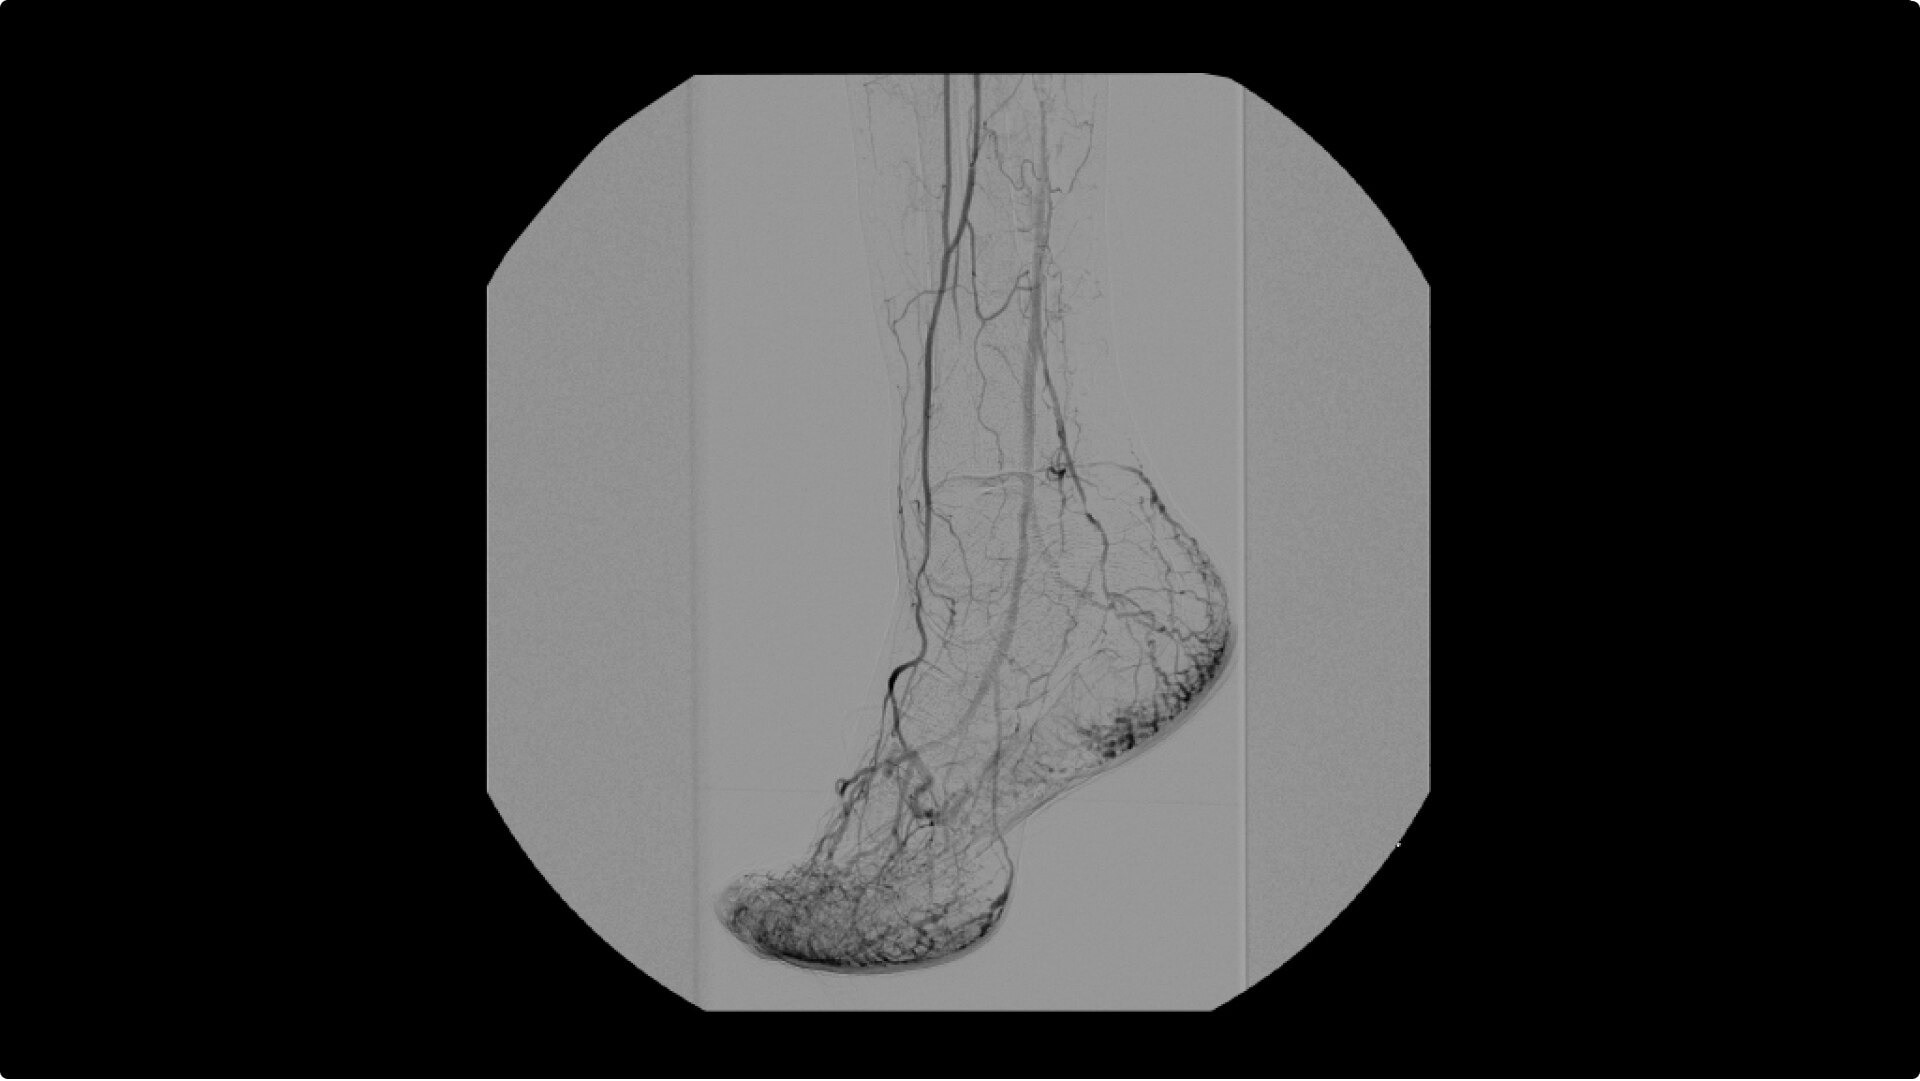

To see vessel stenosis or tips of guidewires, Live Zoom up to 4X during a fluoro or Cine without the additional dose of Mag modes or resulting X-ray tube heat buildup.

Conveniently plan procedures with comprehensive imaging tools to measure percent stenosis, distance, or angles, annotate and draw on images.